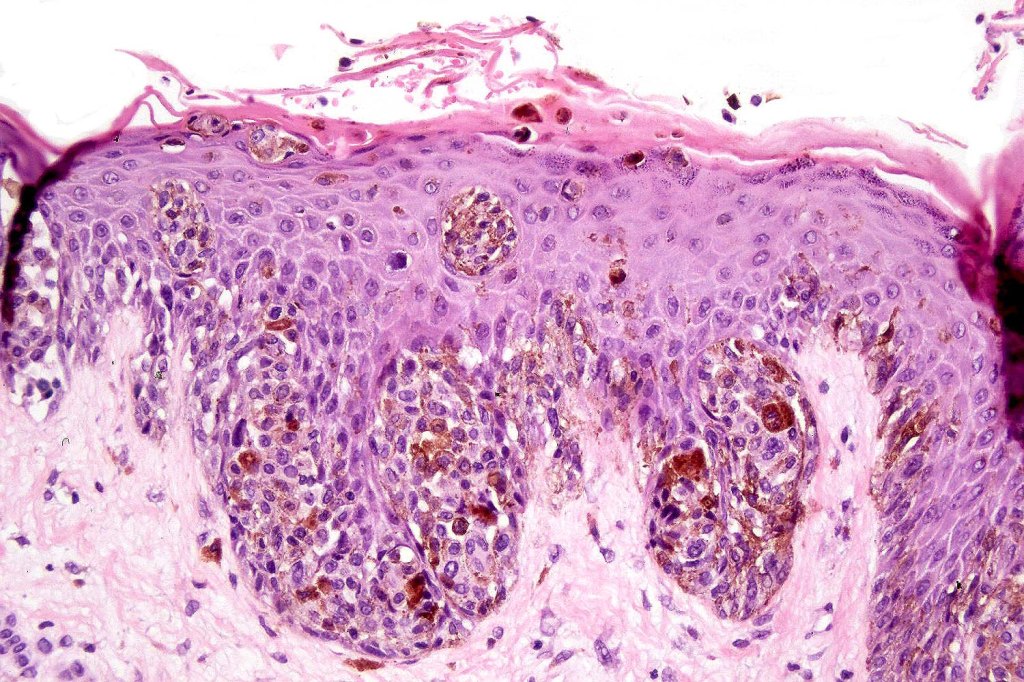

•Junctional/compound

•Large dyscohesive nests with retraction artifact, not restricted to the tips of the epidermal ridges

•Heavy pigmentation (sometimes gray/green)

•Bridging common, often over multiple rete ridges

•Variable atypia (can be marked)

•Central pagetoid spread